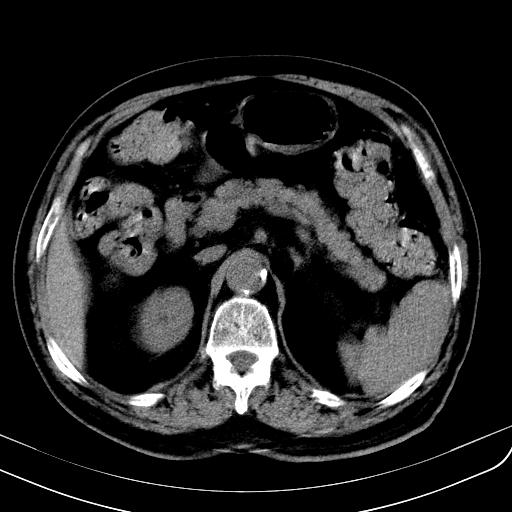

胃底靠近胃大弯处可见一圆形软组织影,直径为3.45cm,ct值约为30.1hu

间质瘤或神经鞘瘤。

考虑胃底平滑肌瘤。血肿不除外。